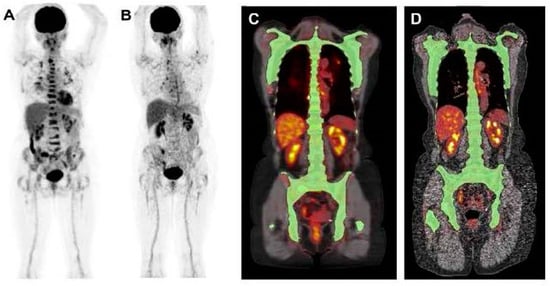

The efficacy of [18F]FDG PET/CT in the evaluation of myeloma osteolytic lesions has been validated (Figure 2 and Figure 3), with recorded sensitivity and specificity ranging between 80% and 100% [8,11]. In a systemic review including eighteen studies with 798 patients, [18F]FDG PET exhibits higher sensitivity for detecting myeloma bone lesions compared to WBXR [14]. In another systemic review by Ragerlink et al. [15], all of the imaging modalities demonstrated a greater detection rate when compared to WBXR, showing up to an 80% increase in the rate of osteolytic lesion detection: MRI (1.12–1.82), CT (1.04–1.33), PET (1.00–1.58), and PET/CT (1.27–1.45). Some recent guidelines, including those from the European Myeloma Network and the 2016 update of the European Society of Medical Oncology guidelines, advocate for the use of whole-body low-dose CT as the preferred method to evaluate lytic bone lesions in MM [15]. There are, however, few studies that have prospectively compared whole-body low-dose CT with [18F]FDG PET/CT [11]. According to the latest IMWG consensus guideline, the initial diagnostic evaluation of myeloma patients can be performed by [18F]FDG PET/CT instead of low-dose whole-body CT (IV level of evidence) [11]. In addition, as per the NCCN guidelines, both low-dose CT and [18F]FDG PET/CT are considered appropriate options for the initial assessment of myeloma patients [10].

Figure 2.

This figure illustrates the crucial role of [18F]FDG PET in evaluating skeletal disease in MM. The case is of a 60-year-old man newly diagnosed with MM. [18F]FDG PET revealed cervical lymphadenopathies and multiple active lesions with varying degrees of [18F]FDG uptake in the skeleton (A). An active lesion in the sternum (indicated by arrows) was detected on PET and PET/CT (A,B,D), but was not clearly visible on CT alone (C). The image was sourced from PMID: 31084774 (Figure 1), and permission was granted for its use.

Figure 3.

This figure demonstrates the high sensitivity of [18F]FDG in detecting active MM lesions. The images present [18F]FDG PET (left) and Na[18F]F scan (right) of a 60-year-old man diagnosed with MM. The whole-body [18F]FDG PET scan reveals numerous active lesions in the skeleton and extramedullary sites (A). The whole-body Na[18F]F PET scan did not identify most of the lesions detected by [18F]FDG PET (B). The image was sourced from PMID: 31084774 (Figure 2), and permission was granted for its use.